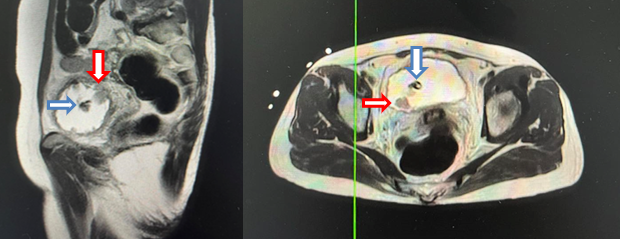

- Cộng hưởng từ tiểu khung:

Hình 3: Chụp cộng hưởng từ ổ bụng, tập trung tiểu khung (13/06/22): Hình ảnh u bàng quang T2aNxMx, vị trí 7h có nốt kích thước 12x16mm (mũi tên đỏ), trong lòng có hình ảnh sonde tiểu (mũi tên xanh), không có sỏi

- Cộng hưởng từ ổ bụng:

Hình 4: Cộng hưởng từ ổ bụng (02/02/23): Không thấy tổn thương nghi ngờ thứ phát tại bàng quang (mũi tên)